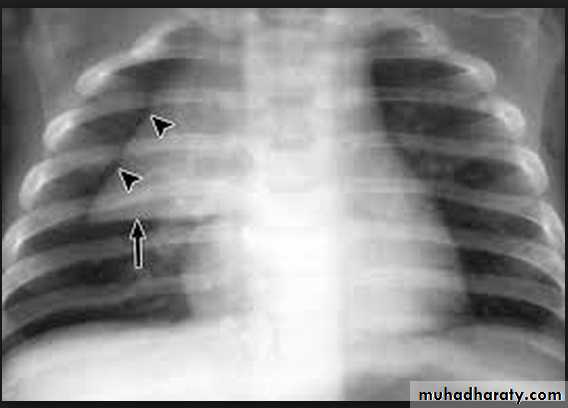

Kerley A lines (Arrows), Kerley B lines (arrowheads)